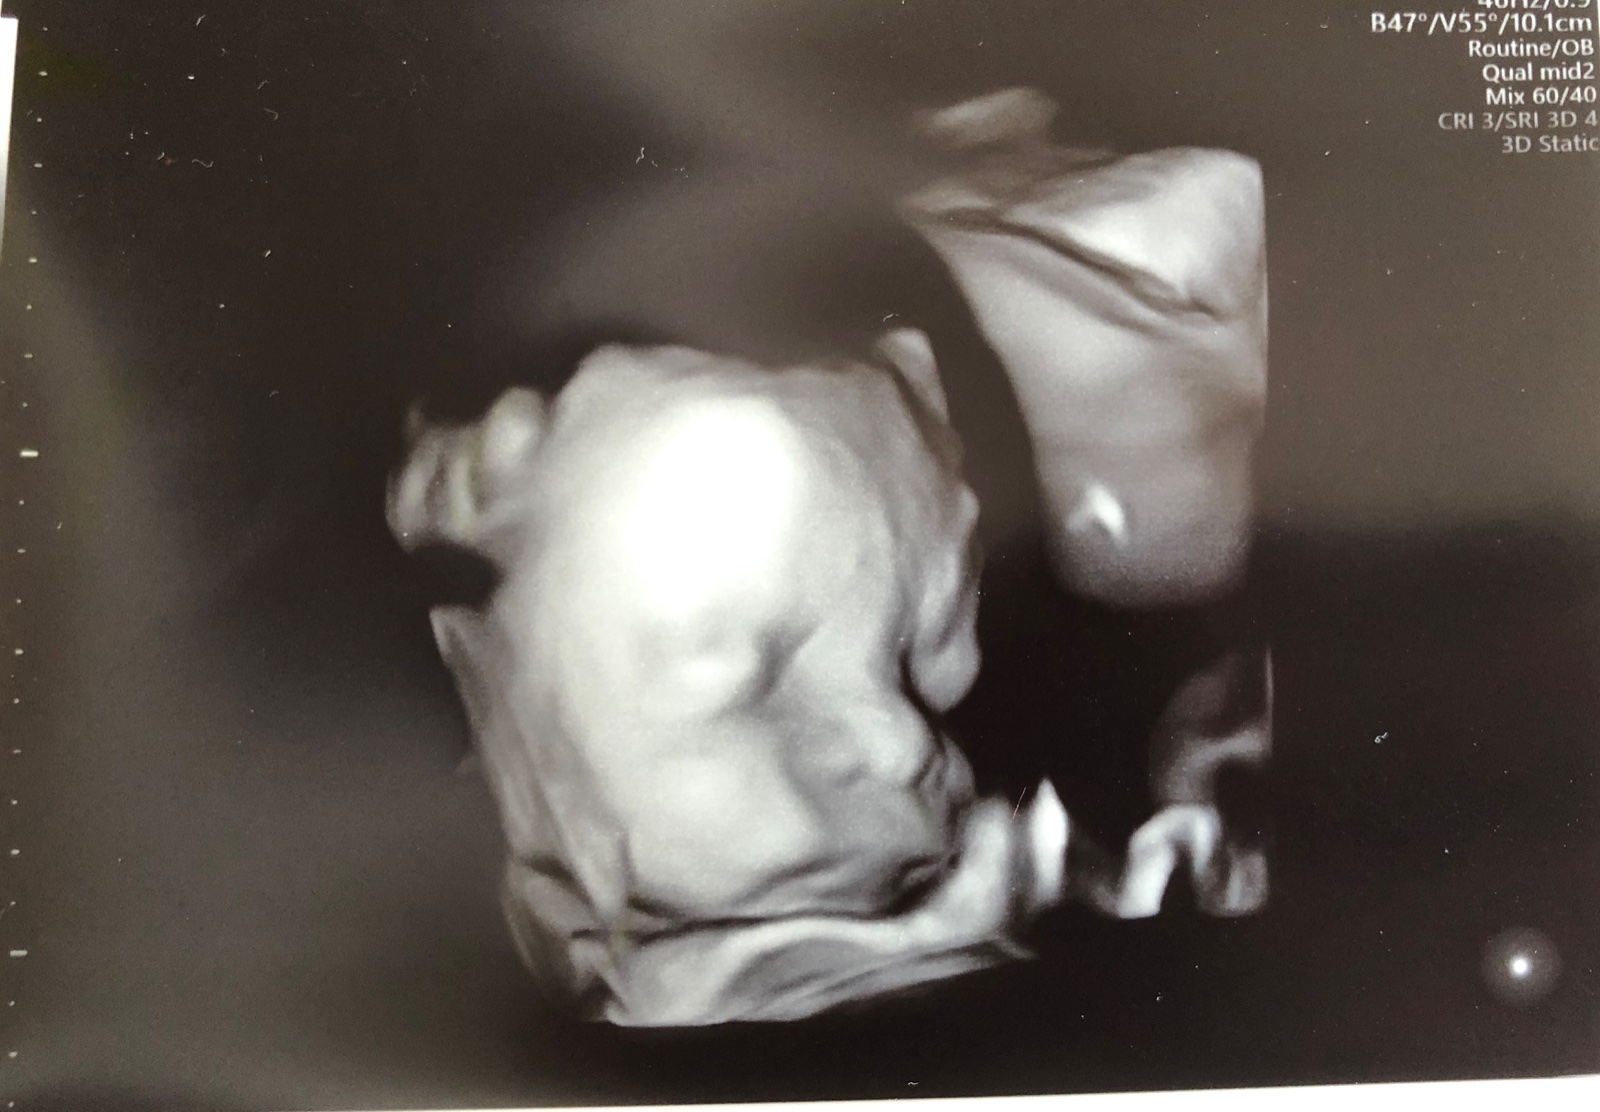

@luckynko44 jejooo, gratulujem a drzim palceky nech rastiete dalej ❤️❤️❤️ Stale si pametam ten den, ked sme riesili ziadosti do CAR. Dnes mame obe pod srdcami dalsie srdiecka. Ja som bola dnes na kontrole, uz sme 25tt 🥰 na foto je kopia mojho manzela, cely tata.